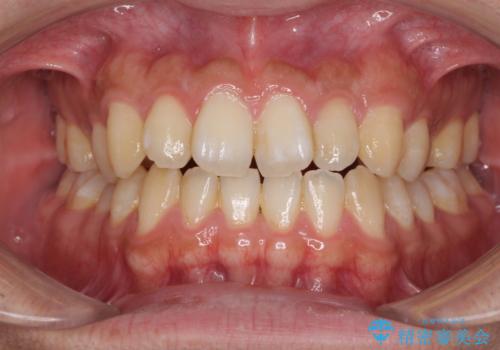

- 上下の前歯の叢生を気にして来院された患者様です。

前歯のみの矯正治療を希望でしたが、上顎臼歯が舌側転位していたため、上顎は全体を、下顎は前歯のみを矯正治療することとしました。

矯正治療は上下全顎を行うことが大前提ですが、費用などの点から、今回は部分矯正を選択することとなりました。

患者様本人は咬みにくさを感じていないようですが、部分矯正は咬み合わせの改善が困難であることが多く、咬みにくさが残ることがあります。